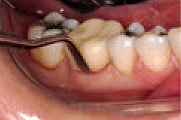

Figure 3

Roll Protemp™ Crown Temporization Material between gloved fingers

to soften.